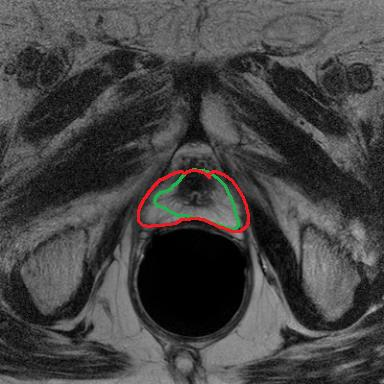

Modern deep neural networks struggle to transfer knowledge and generalize across diverse domains when deployed to real-world applications. Currently, domain generalization (DG) is introduced to learn a universal representation from multiple domains to improve the network generalization ability on unseen domains. However, previous DG methods only focus on the data-level consistency scheme without considering the synergistic regularization among different consistency schemes. In this paper, we present a novel Hierarchical Consistency framework for Domain Generalization (HCDG) by integrating Extrinsic Consistency and Intrinsic Consistency synergistically. Particularly, for the Extrinsic Consistency, we leverage the knowledge across multiple source domains to enforce data-level consistency. To better enhance such consistency, we design a novel Amplitude Gaussian-mixing strategy into Fourier-based data augmentation called DomainUp. For the Intrinsic Consistency, we perform task-level consistency for the same instance under the dual-task scenario. We evaluate the proposed HCDG framework on two medical image segmentation tasks, i.e., optic cup/disc segmentation on fundus images and prostate MRI segmentation. Extensive experimental results manifest the effectiveness and versatility of our HCDG framework.